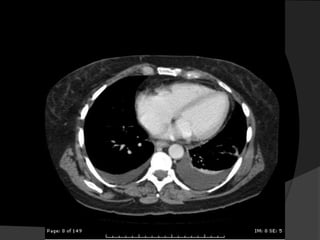

Avaliação InicialEstudos ultra-sonográficosRadiografias em decúbito lateral (Laurel)Tomografia Computadorizada (TC) para analisar o parênquima pulmonar subjacente ou mediastino.

Avaliação InicialEstudos ultra-sonográficosRadiografiasem decúbito lateral (Laurel)Tomografia Computadorizada (TC) para analisar o parênquima pulmonar subjacente ou mediastino.